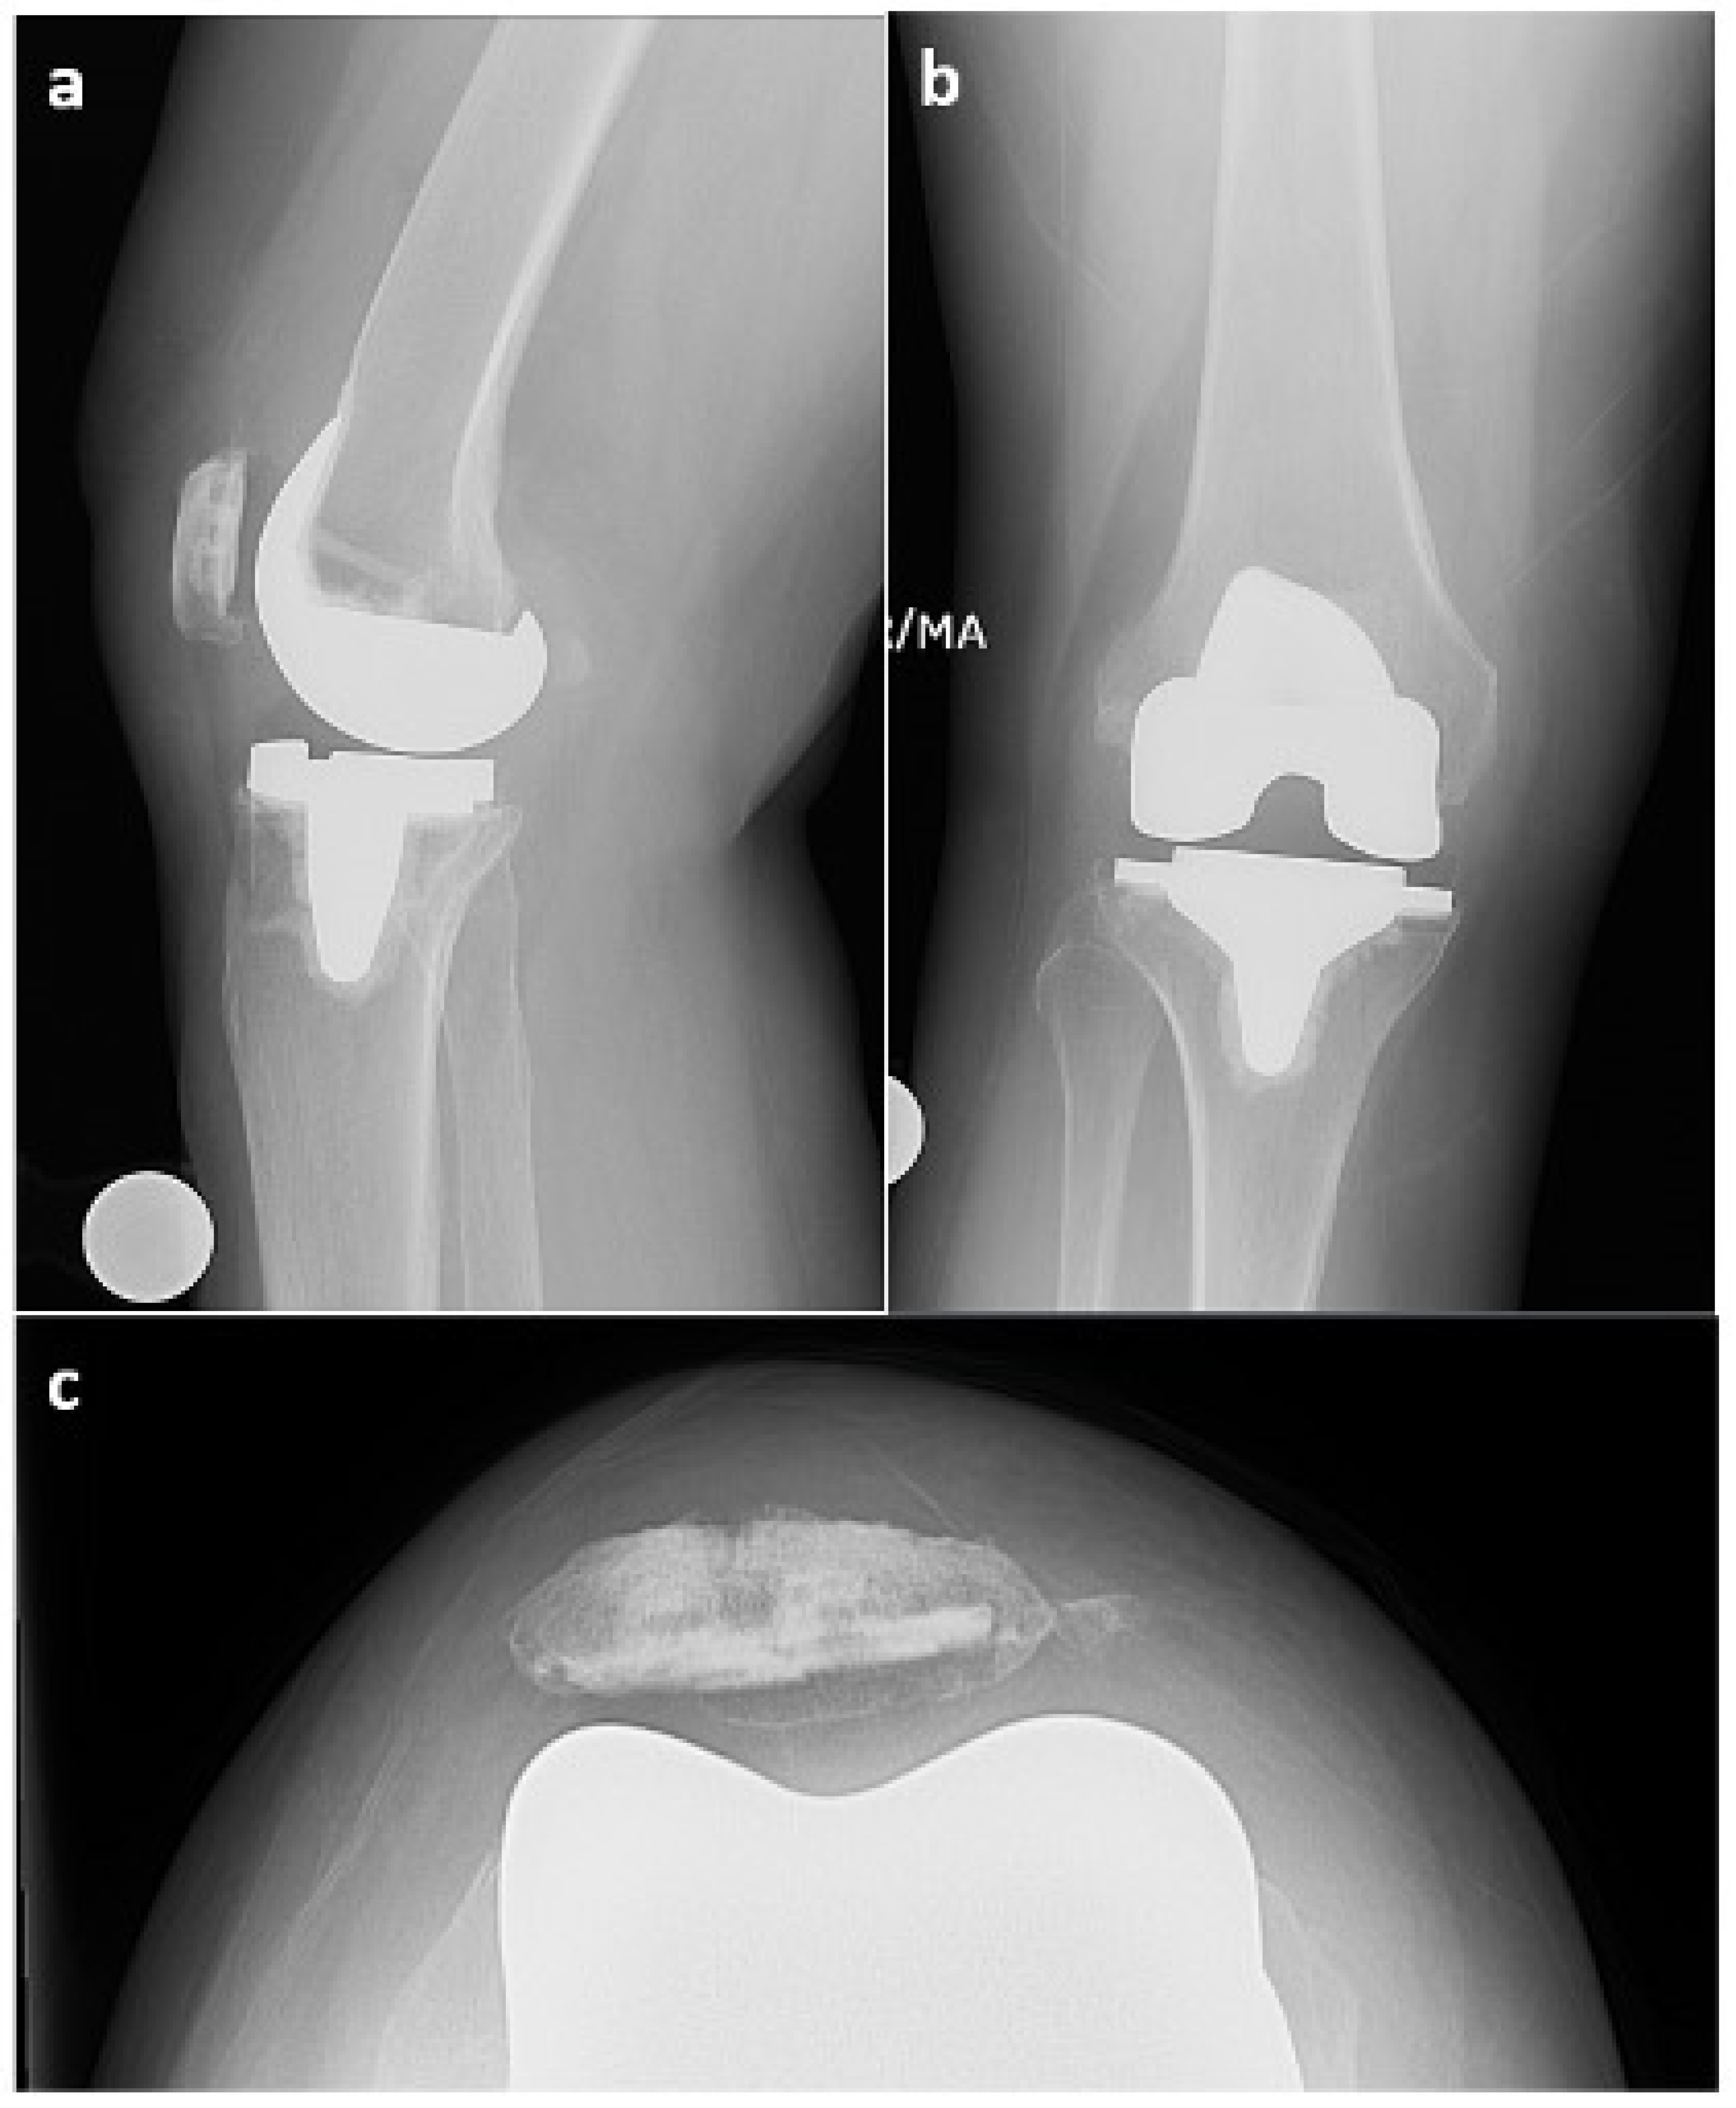

This case report refers to a 62-year-old woman who received a right TKA for primary osteoarthritis (OA) in August 2018 at the age of 58 years at an outside hospital. Informed consent was obtained from the patient with an explanation that the data concerning her case would be submitted for publication. The patient’s x-ray and MRI images showed no evidence of SC prior to her TKA surgery, as seen in Figure 1. The synovial tissue samples of the knee joint obtained during her index right TKA surgery also showed no evidence of SC, but showed synovial hyperplasia with lymphocytic infiltration, as this can occur in the context of degenerative joint disease or in association with RA.

Figure 1. X-ray from 11 June 2018 ((a)—lateral view, (b)—anterior–posterior view) and MRI from 13 March 2017 ((c)—axial view, (d)—sagittal view); right knee shows knee osteoarthritis with no sign of synovial chondromatosis prior to TKA in August 2018.